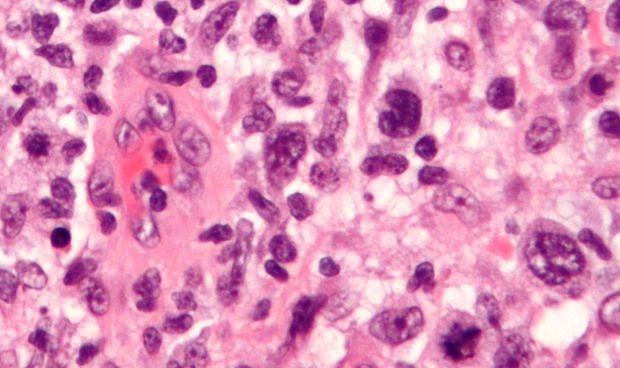

Mientras algunos países planifican la estrategia de la campaña de vacunación contra el Covid-19, los científicos no descansan en encontrar una fórmula alternativa para frenar la pandemia. En esta línea, ha surgido un nuevo hallazgo, a partir de una estrategia computacional de detección de medicamentos, el cual ha determinado que el pralatrexato, un fármaco que se usa en quimioterapia para tratar los linfomas, podría servir para inhibir la replicación del SARS-CoV-2.

Una investigación realizada por Haiping Zhang, de los Institutos de Tecnología Avanzada de Shenzhen, en China, y publicada en la revista PLOS Computational Biology, da cuenta de una nueva estrategia computacional de detección de fármacos combinada con experimentos de laboratorio, la cual sugiere que el pralatrexato, un medicamento de quimioterapia desarrollado originalmente para tratar el linfoma, podría potencialmente reutilizarse para tratar Covid-19, aunque no se descarta que esta acción desencadena efectos secundarios.

En esta línea, los investigadores combinaron múltiples técnicas computacionales que simulan interacciones fármaco-virus desde perspectivas diferentes y complementarias. Utilizaron este enfoque para seleccionar 1.906 medicamentos por su capacidad potencial para inhibir la replicación del coronavirus al dirigirse a una proteína viral llamada ARN polimerasa dependiente de ARN (RdRP). Con la nueva estrategia, solo cuatro pasaron el corte, que posteriormente fueron probados contra el Covid-19 en el laboratorio. Y de esos, el pralatrexato y la azitromicina, lograron la inhibición con éxito, siendo el primero el medicamento más fuerte para impedir la replicación.